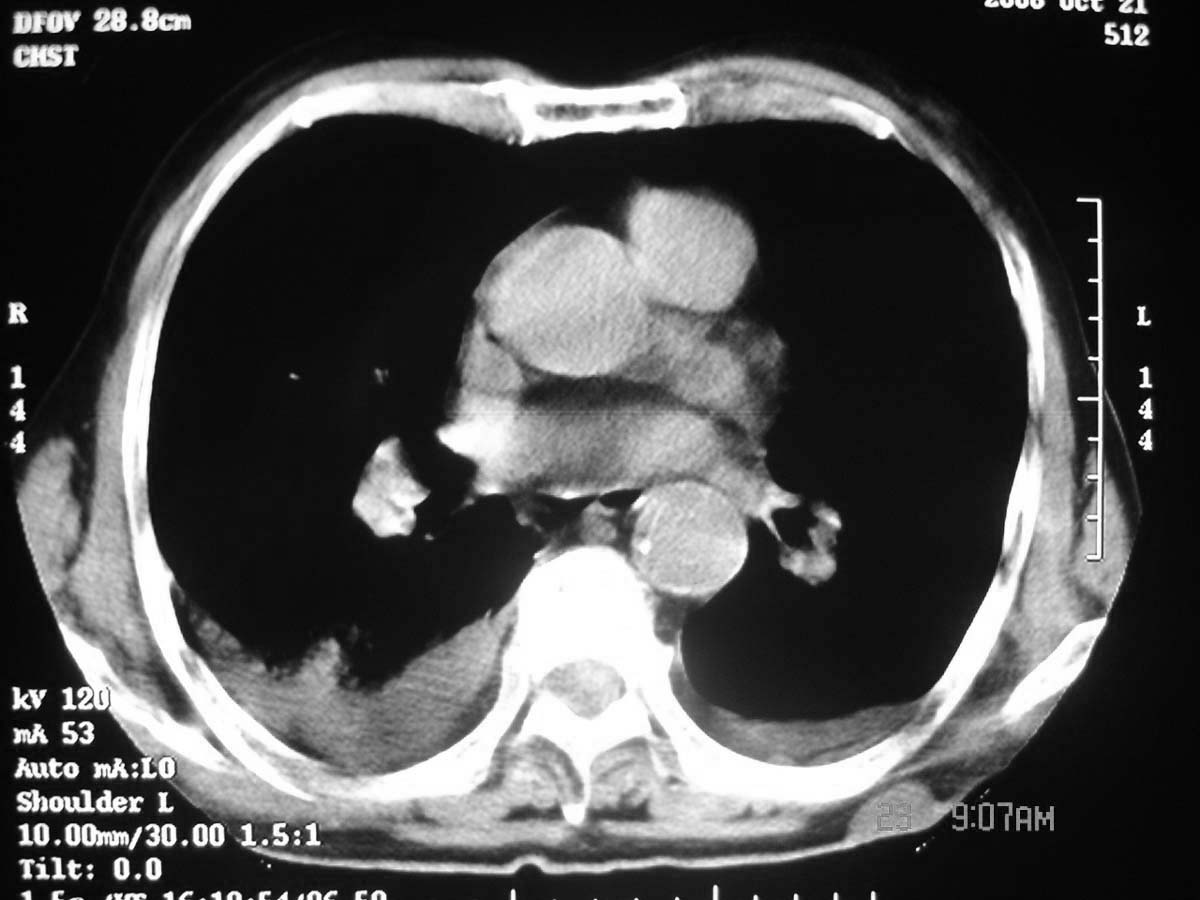

以下是引用守望可可西里在2006-11-23 14:33:00的发言:[br][br] 糖尿病病人很容易继发结核,病人又有双侧胸膜增厚、粘连、胸腔积液以及双上肺的斑片状、条索状影结核病灶影,以一元论考虑,右下肺病变首先考虑干酪性肺炎,可以正规抗炎治疗后复查,排除一般的肺炎。